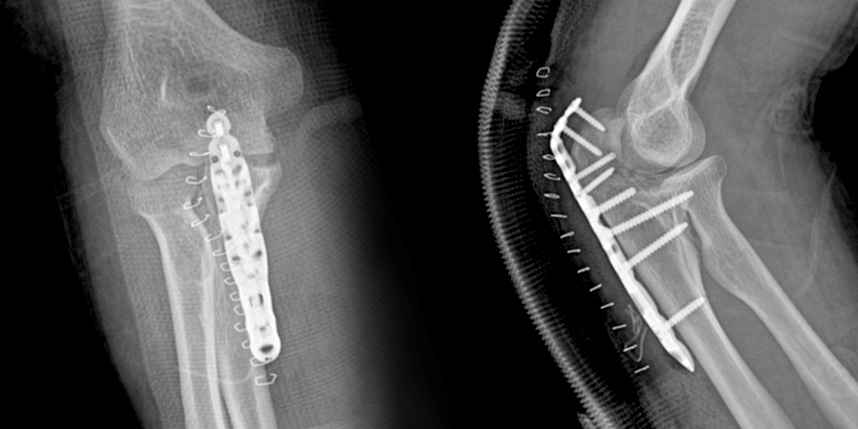

손목 골절